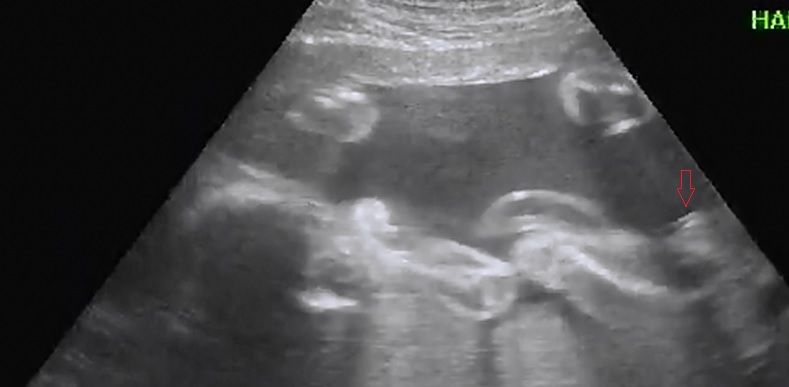

maybe girl but not the best shots to guess from xx

girly I think

Maybe girl, but not the best photos.

strong girl lean. don't see anything boy about these pictures. not 100% cause of picture quality, but would be surprised if this turned out to be a boy.